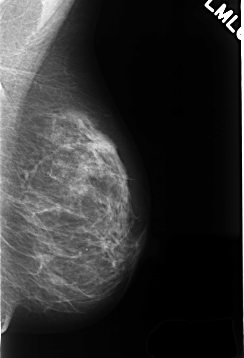

C_0363_1.LEFT_MLO

LEFT_MLO LINES 4288 PIXELS_PER_LINE 2920 BITS_PER_PIXEL 12 RESOLUTION 50 NON_OVERLAY